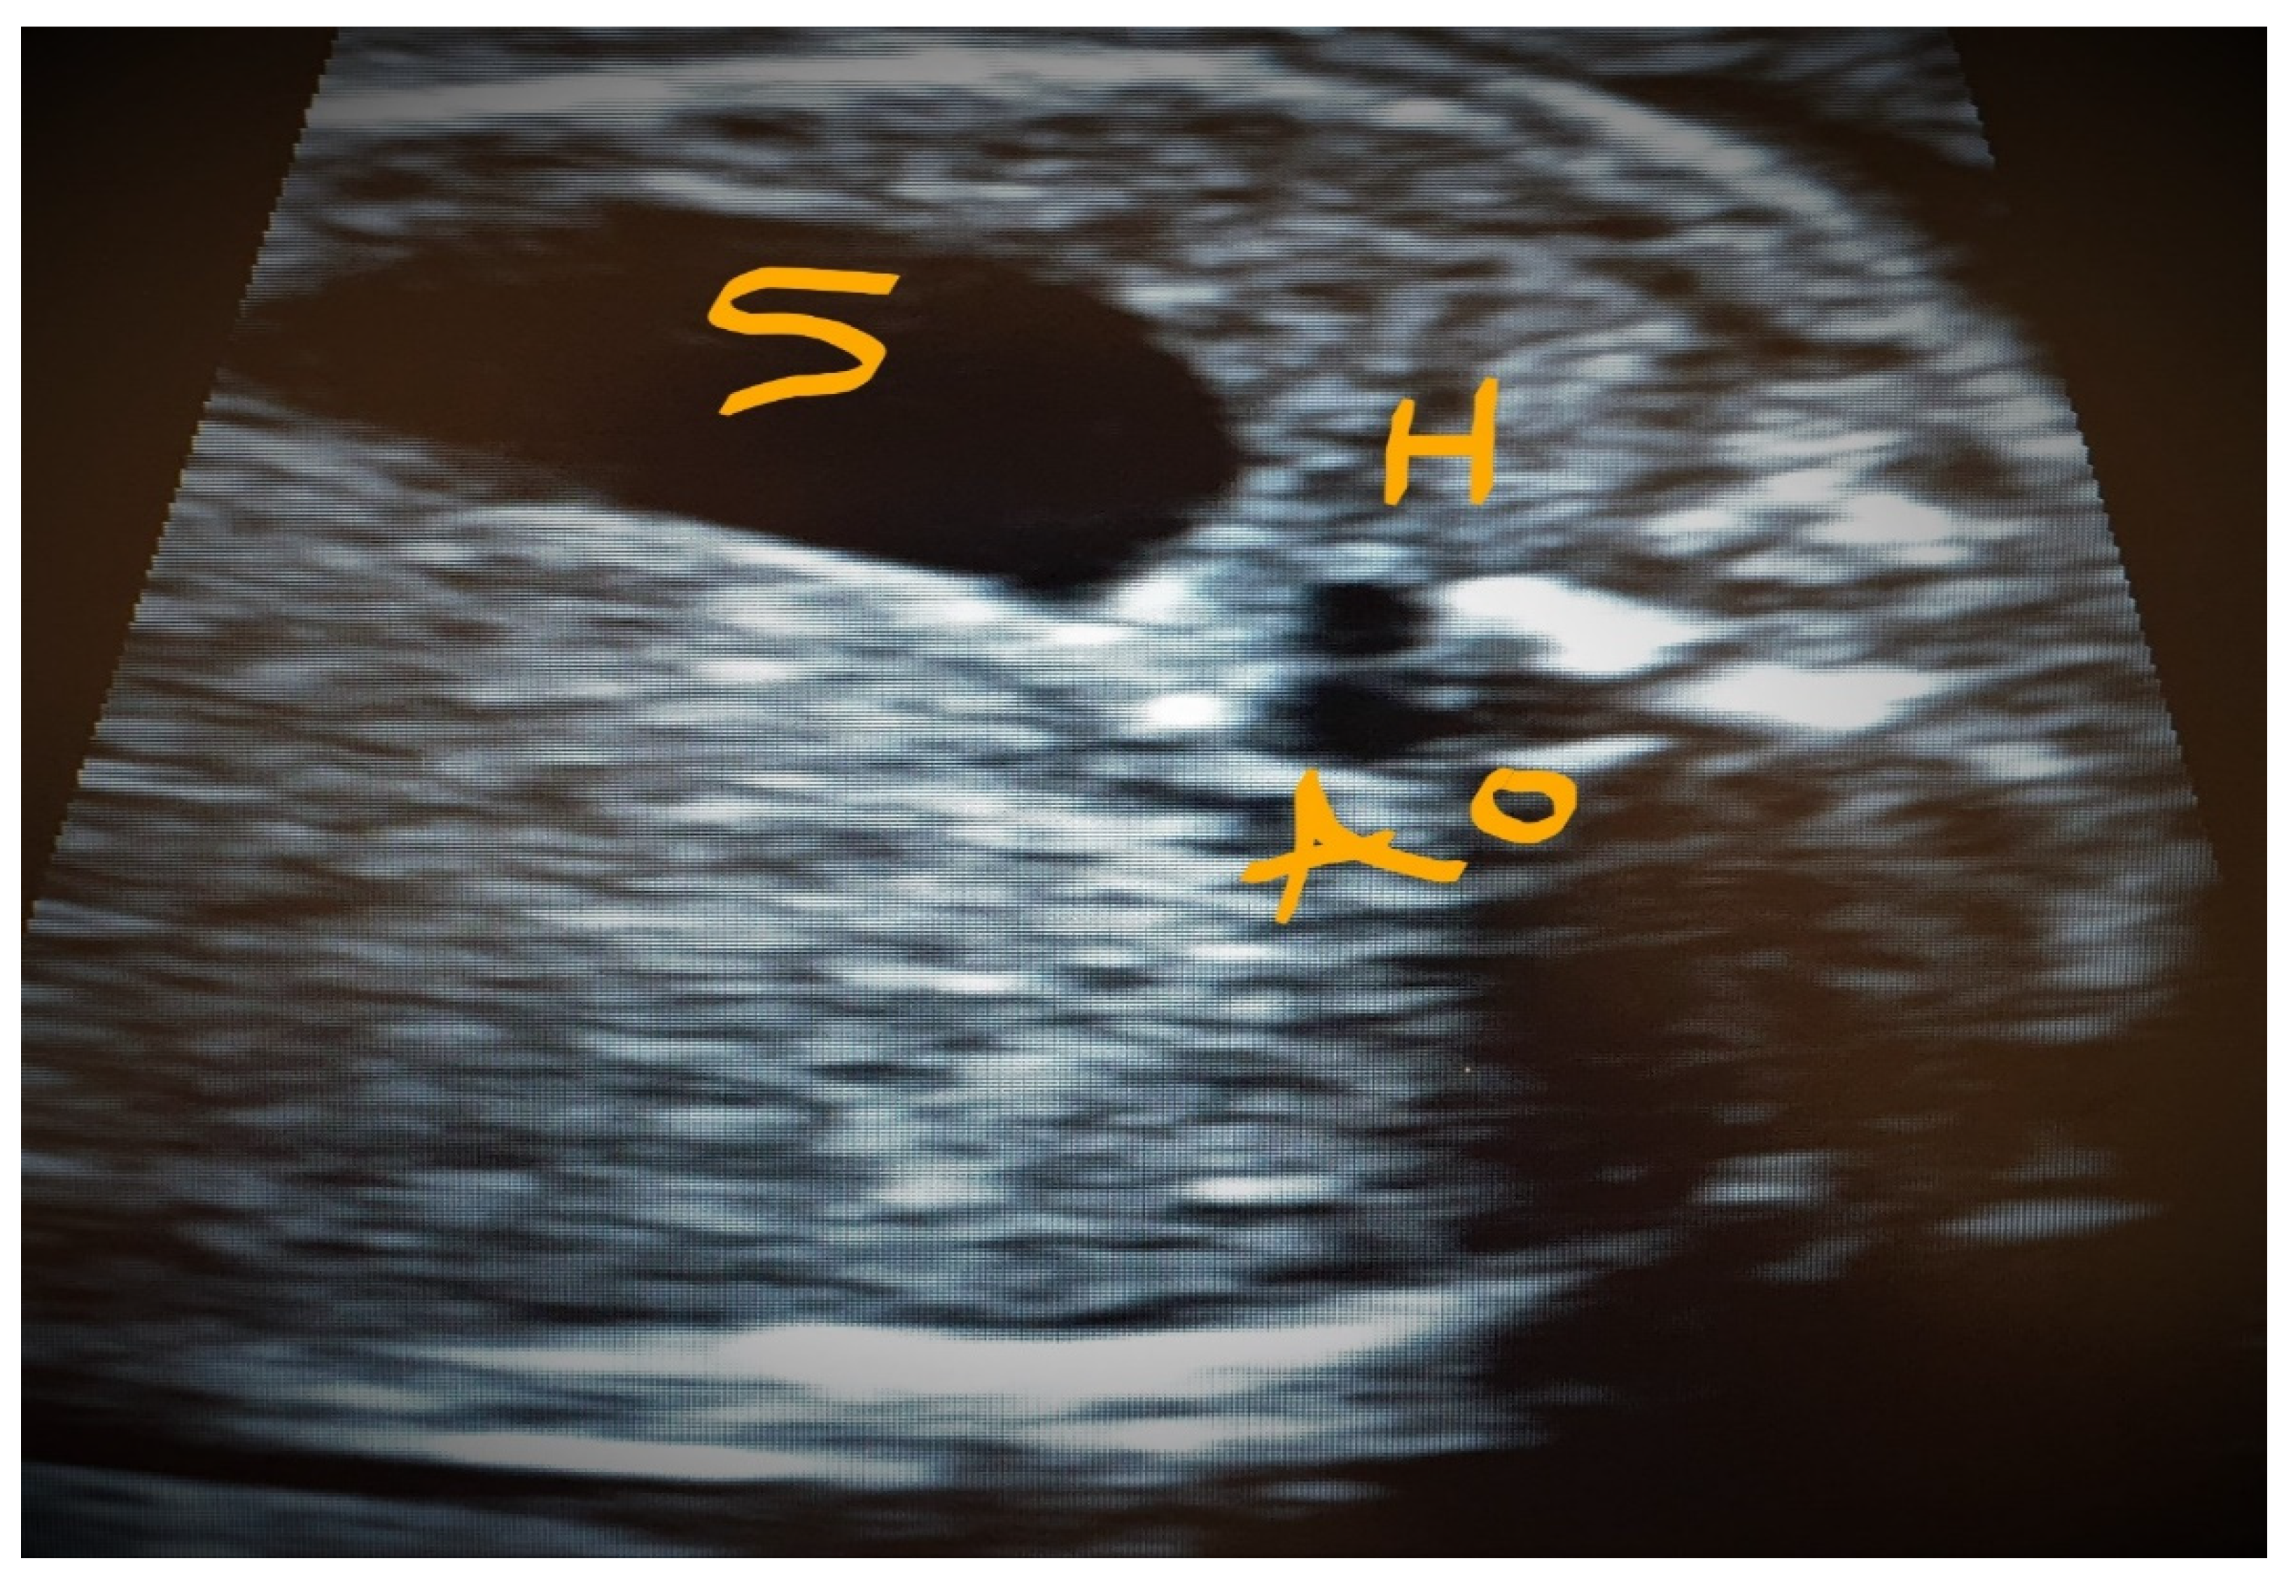

4.4. Case 4